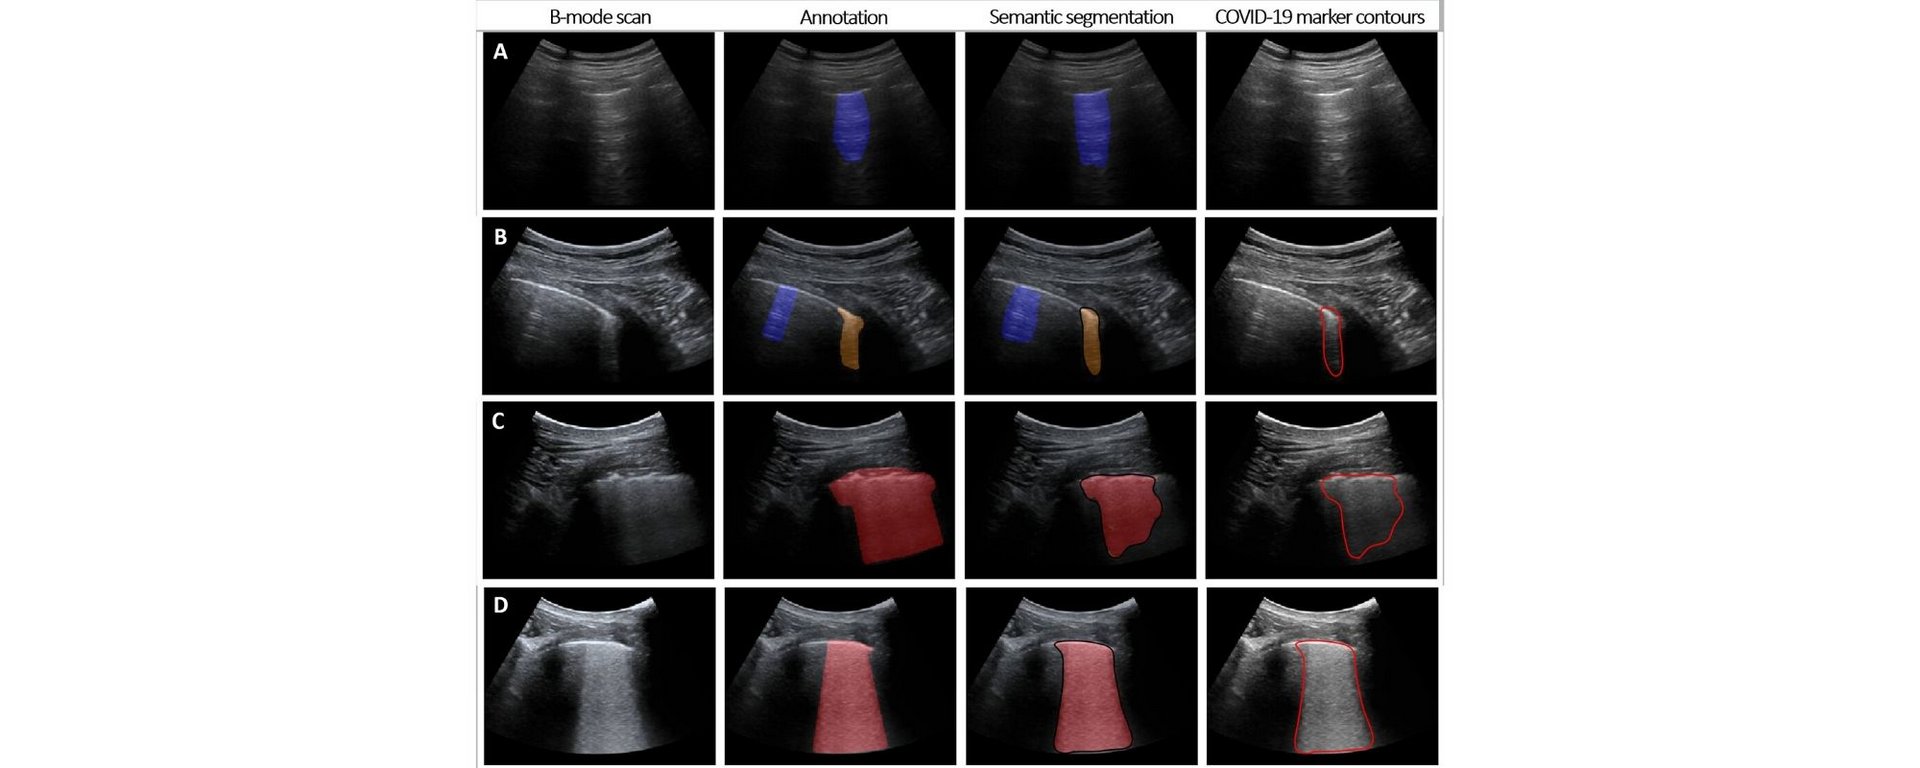

Simple ultrasound provides crucial support for COVID-19 testing within minutes